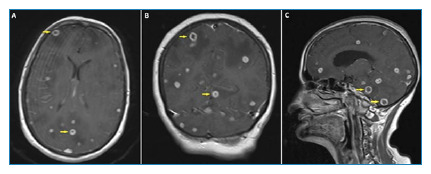

颅内结核瘤伴结核性脑膜炎。

Intracranial Tuberculomas Associated with Tuberculous Meningitis.